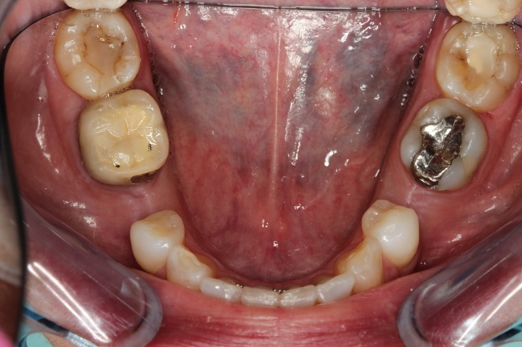

Figure 10 through Figure 13 show the preoperative x-ray and the sequence of beginning with healed sites through the surgical placement of the implants. The implants were protected by an Essix-style wound-protection removable retainer for approximately 12 weeks. After the integration phase, the implants and the natural dentition were prepared using traditional crown-and-bridge high-speed diamond and zirconia cutting burs to remove decay and existing restorative materials, to complete and refine the natural-tooth structures to receive full-crown coverage, and to prepare and refine gingival margins of the zirconia implants where needed.

Fig 10. Preoperative panoramic radiograph.

Figure 10

Fig 11. Preoperative healed sites.

Figure 11